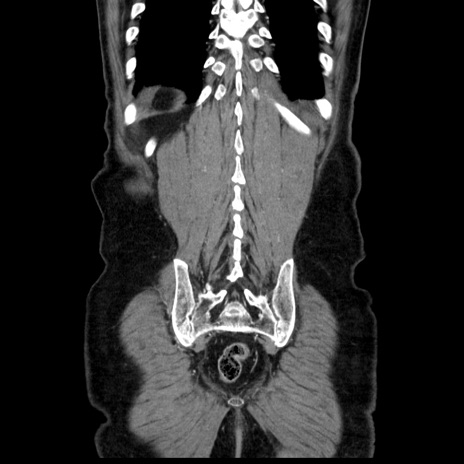

症例30(冠状断像)

【症例】80歳代男性

【主訴】臍周囲痛

【現病歴】約6時間前から臍下部痛が出現。次第に腹部膨隆・背部痛も生じてきたため来院。背部痛の場所は変化しない。

【既往歴】腎盂腎炎

【身体所見】意識清明、BT 36.3℃、BP  131/87mmHg、P 87bpm、SpO2 100%(RA)、臍周囲自発痛・圧痛あり、反跳痛なし、自発痛部位に一致して板状硬あり、腹部膨隆、腸雑音減弱、CVA tenderness両側陰性。

【データ】WBC 19600、CRP 0.33